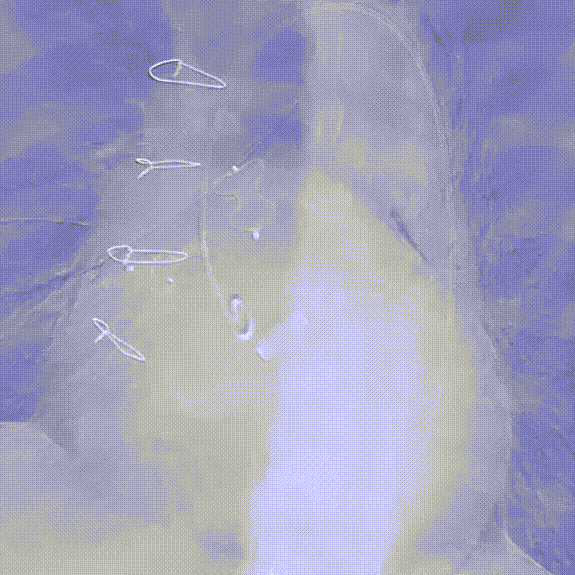

术后CT评估

1.Aortic Wrapping技术目前仍是主动脉根部手术常用技术,能够有效减少术中止血困难问题,且缩短手术时间及体外循环时间,但术后确有部分患者出现远期漏口开放导致心衰包裹腔扩大等问题,需要进一步治疗。经皮介入封堵技术较再次开放手术在手术创伤和围术期安全性具有明显微创优势。

3.通过系列病例研究,完善的术前影像分析能够提高微创封堵手术技术成功率并缩短手术时间,且采用经皮封堵技术能够有效封堵此类吻合口漏,近期临床结果良好,技术可行。